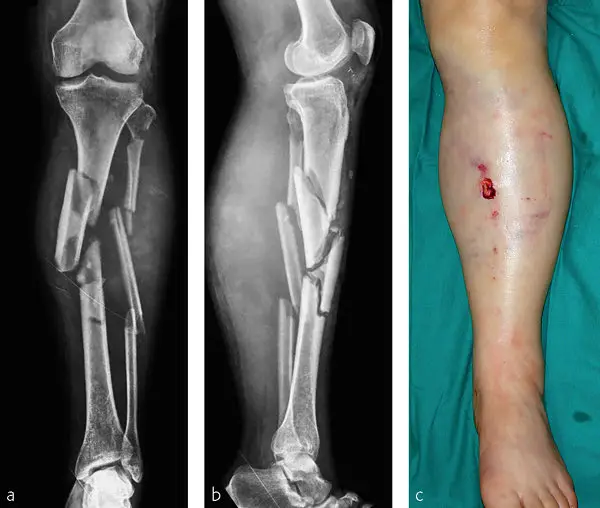

He then revealed what the injury is commonly known as: "This is called an external fixator (‘x-fix’) and is being used to help stabilise the fractured tibia (and maybe more)."

He then shared snaps of a similar injury, noting that 'it's not hers', but that it gives fans a good idea of how serious the fall was.

Warning: Graphic Images

Vonn revealed that she 'sustained a complex tibia fracture', which while stable, would need several surgeries to fix properly.